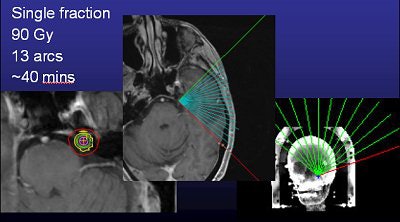

![]() |

| Above, frameless radiosurgery for TN. Below, three months after treatment. Images courtesy of Dr. Kevin Murphy and the University of California, San Diego, department of radiation oncology. |

Murphy's list of linac shortcomings is, well, short. "I trained on (gamma knife). To train on a (Trilogy) system that was frameless and not proven was a hard thing to do. The dose is really high (90 Gy, four times the regular radiotherapy dose, but the same as gamma knife), and it's right next to the brain stem, so if you miss or the patient moves, you're going to fry the brain stem," he said.

To be on the safe side, Murphy said he aims the radiation about a centimeter downstream from the target (away from the brain stem) and does redundant positioning verification.